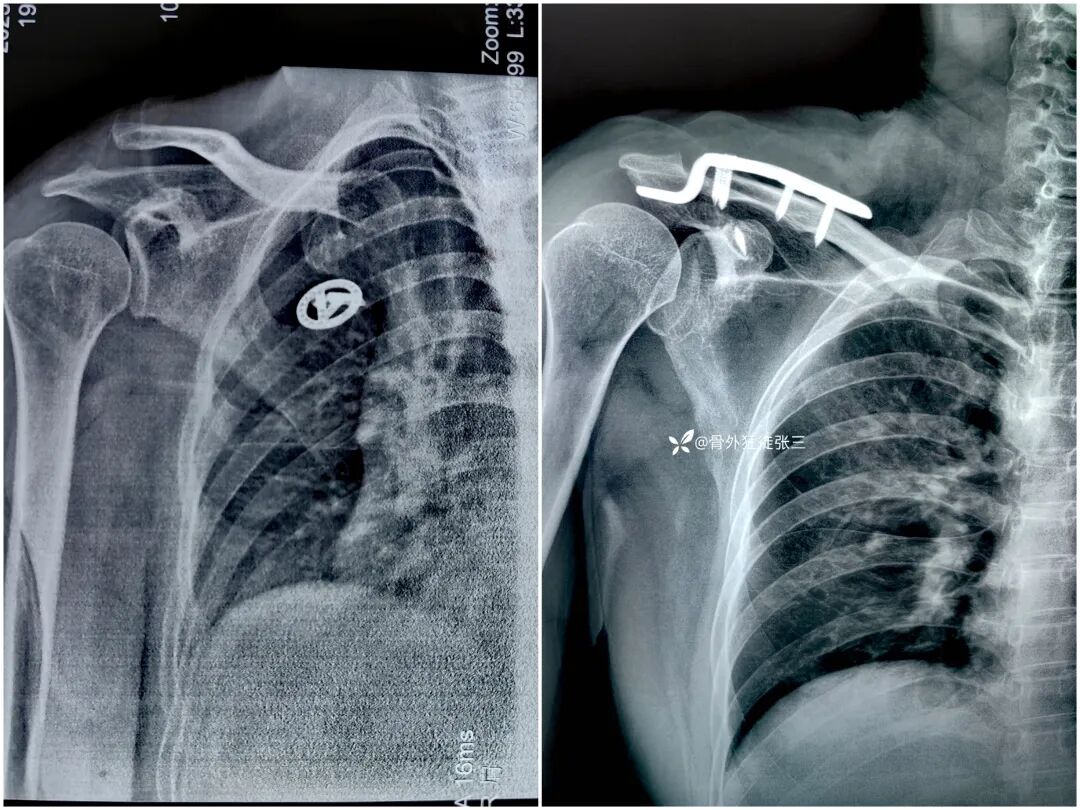

病例一:

钩弧度和深度不合适,肩峰骨溶解